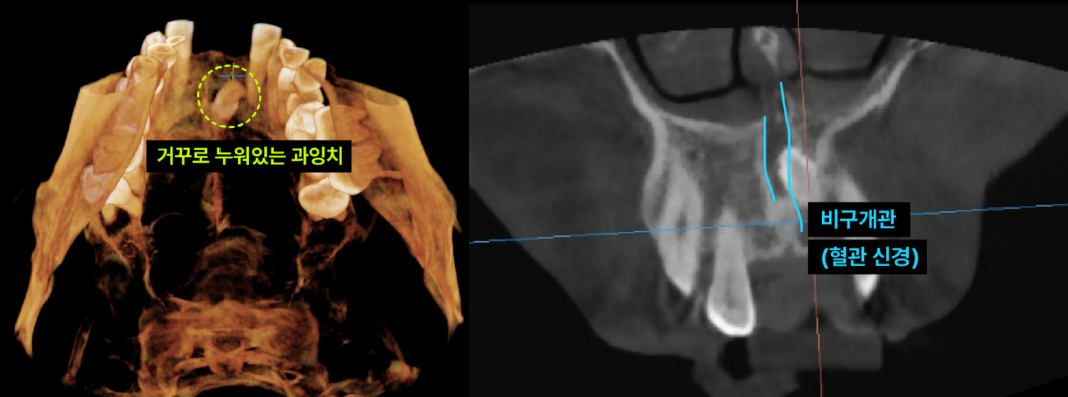

이백점치과의 정밀 진단 환자의 과잉치는 입천장 뼈 속에 거꾸로 누워있었고, 중요한 신경과 혈관이 지나는 '비구개관(Incisive Canal)'을 침범한 상태였습니다. 이처럼 민감한 부위의 매복 과잉치를 제거할 때는 비구개신경 손상이나 출혈에 각별히 주의해야 합니다. 이백점치과는 최신 장비를 활용한 정밀 진단으로 이런 디테일까지 놓치지 않습니다.